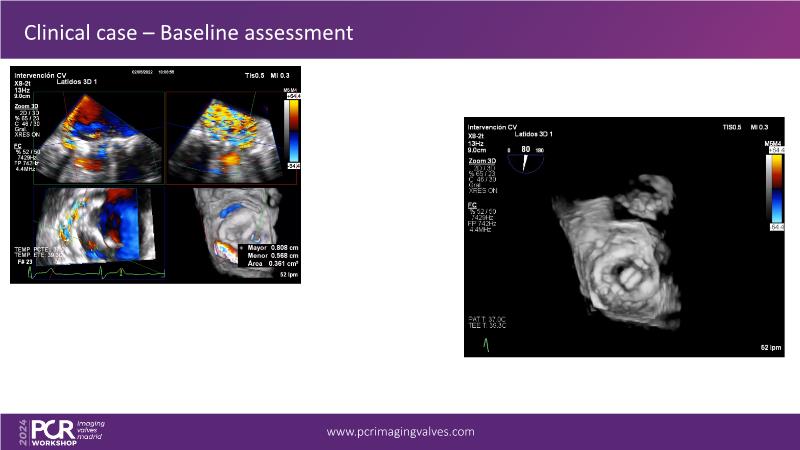

Explore cutting-edge transcatheter valve interventions for mitral and aortic valve disorders, including valve-in-valve procedures and management strategies for paravalvular leakages, and learn about diagnosing and treating mitral annular calcification and transcatheter options in infective endocarditis.

- To get tips and tricks for guidance of transcatheter intervention